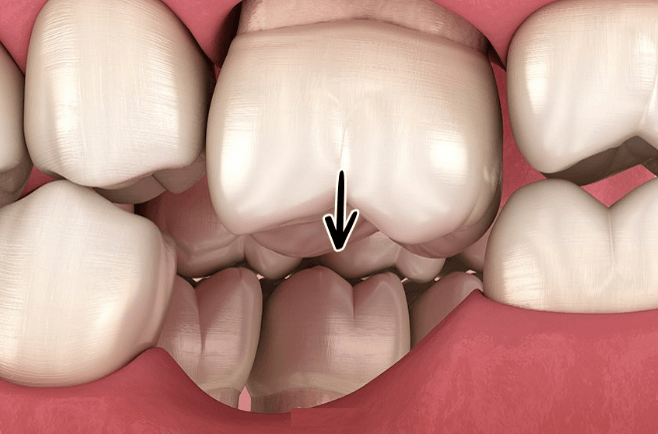

1. 치아의 균열 이상

어금니 치아는 서로 붙어서 힘을 지탱하는 역할을 합니다. 그런데 중간에 어금니를 발치하게 되면 그곳에 빈 공간이 생기고 양 옆에 있는 어금니는 옆으로 서서히 무너지게 됩니다.

이런 경우 음식물이 잘 끼게 되어 옆 이에 충치가 생길 수 있으며, 옆의 치아가 많이 기울게 되면 그 공간이 너무 좁아져서 임플란트 할 수 있는 공간이 좁아져서 별도로 먼저 교정 후 임플란트를 진행해야 하는 상황이 초래합니다. 이에 따라 이중으로 비용이 발생하게 되니 큰 손해입니다.